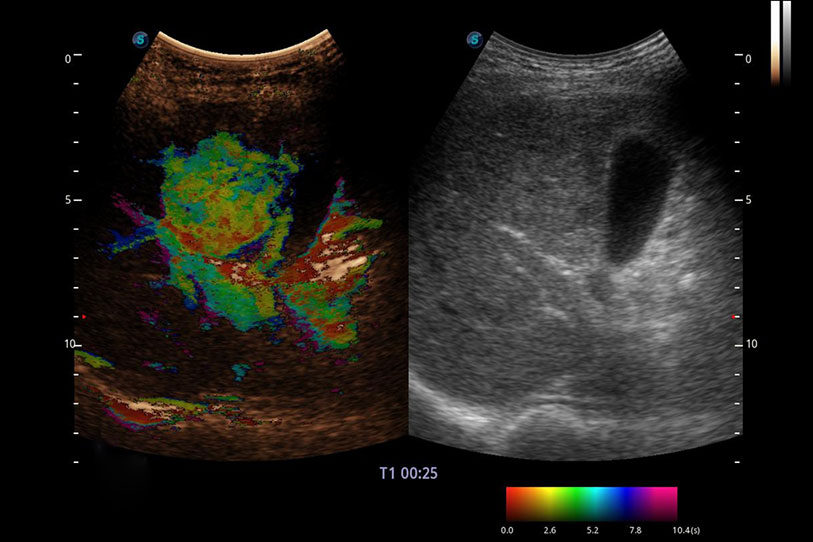

操作簡便,無需高頻度外力作用即可真實反映組織的形變,快速評估腫瘤良惡性。

采用紅、橙、黃、綠、青、藍、紫這七種肉眼最為敏感的色彩,直觀地顯示組織內(nèi)血流灌注的時間先后信息,更精準捕捉血流灌注走行細節(jié)。